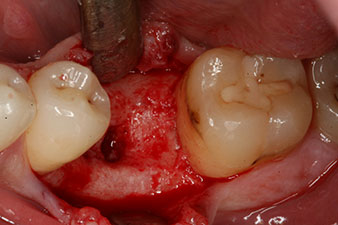

However, six weeks after the extraction incomplete ossification was found after preparation of the mucoperiosteal flap in the region of the former mesial alveolus.

The implant was placed as planned after thorough removal of the granulation tissue (blueSky, bredent).

The torque used for the machine-driven placement was 43 Ncm. In addition, after screwing a measuring post (SmartPeg) specially matched to the implant, the ISQ value was measured with the probe of the W&H Osstell ISQ module.